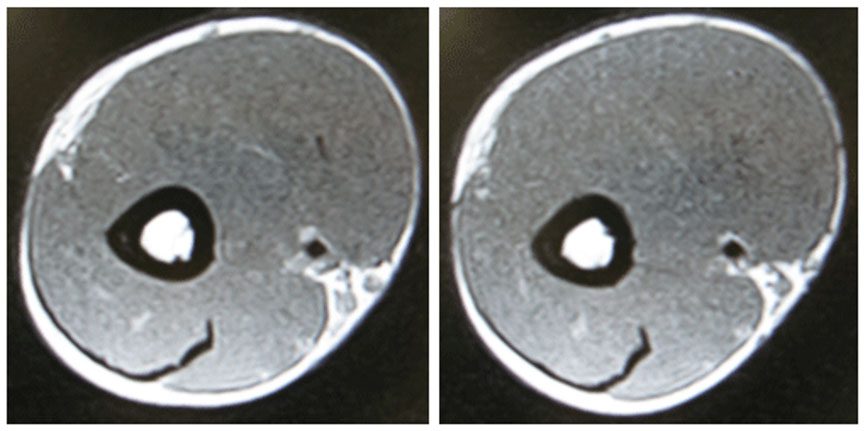

Dr.ヘイキが行った筋肥大に関する研究のMRI画像を見てください。

これは12週間筋力トレーニングを行った腕の断面図です。

外見からはわかりづらいのですが、beforeとafterを比べると3ヶ月で約9%肥大したことが確認できます。

目視では確認できませんが、3ヶ月のトレーニングで腕の筋肉は約9%肥大しました。